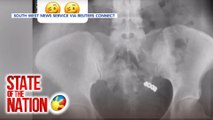

12-anyos na lalaki, patay nang aksidenteng mabaril ang sarili gamit ang service firearm ng amang pulis | SONA